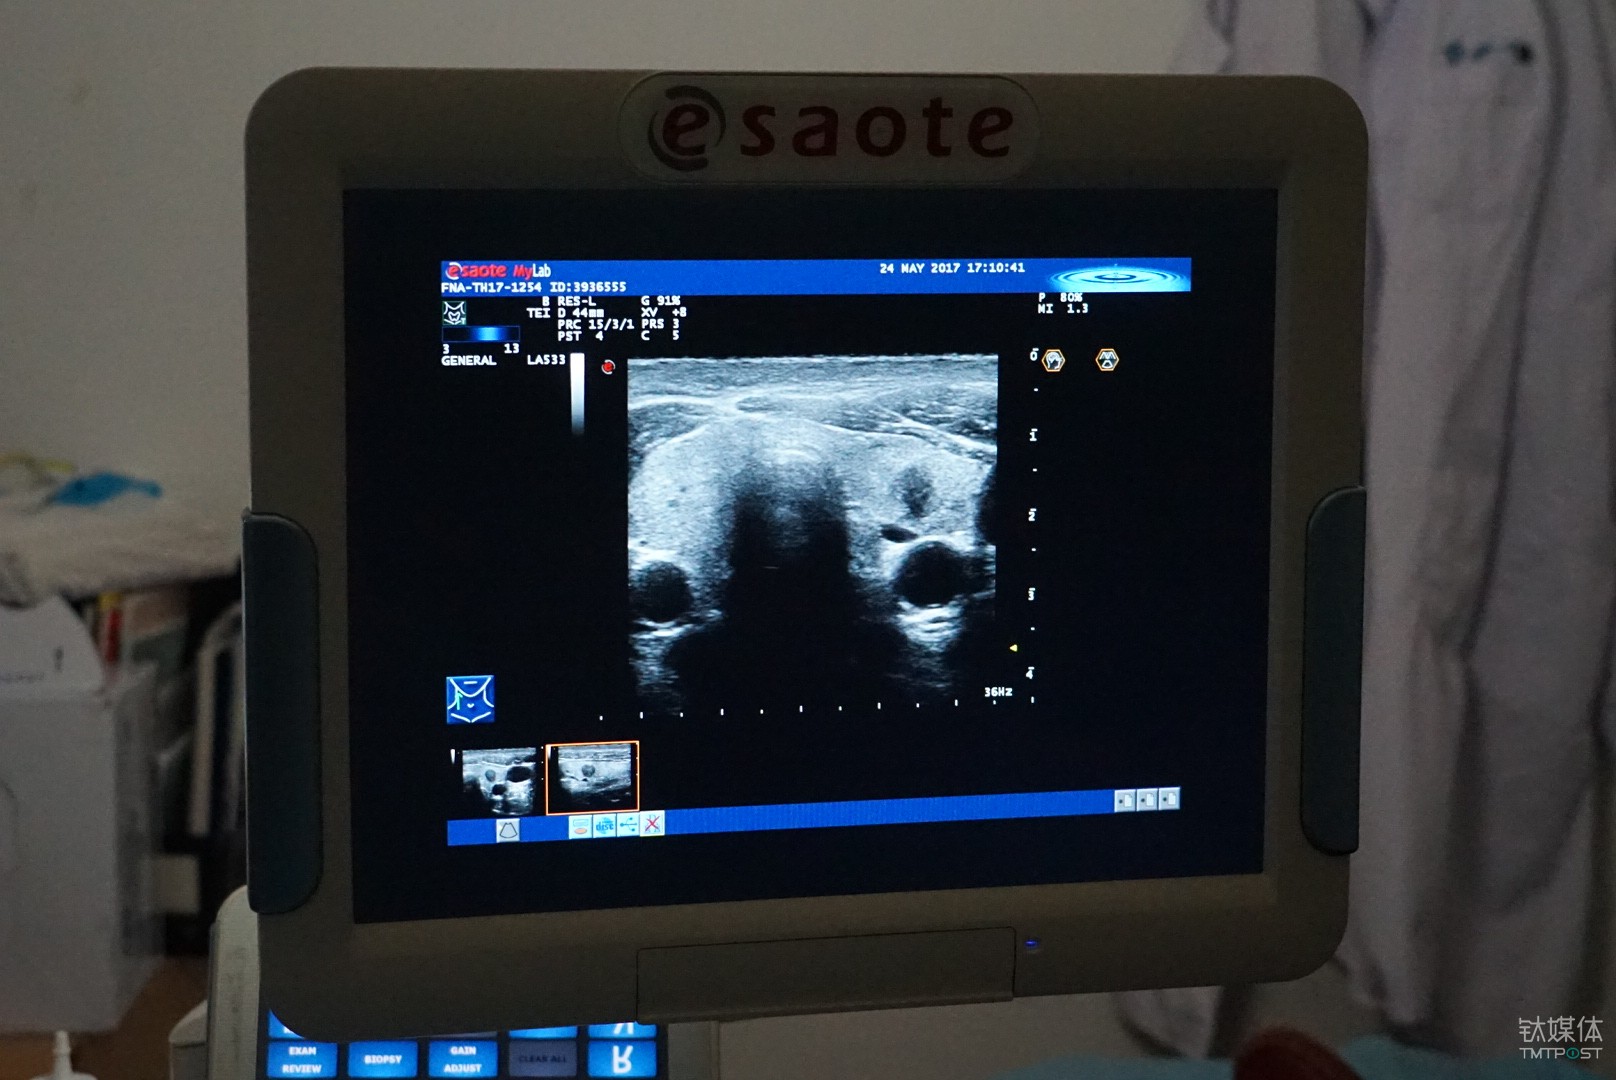

从功能上来说,这是一套基于超声波影象的甲状腺结节良恶性的辅助诊断系统,根据甲状腺结节检查时候拍摄的医学影像的特征,通过对图像的识别和标注,来帮助医生更准确的做出诊断结论。

对于甲状腺结节的检查目前主要依靠超声的方式,相较于CT和核磁,超声的好处是便宜、灵活、无副作用,所以它也是目前临床医学使用最为广泛的一种检测手段,不足之处是图像不清楚、造影比较大,它对医生的要求就比较高。